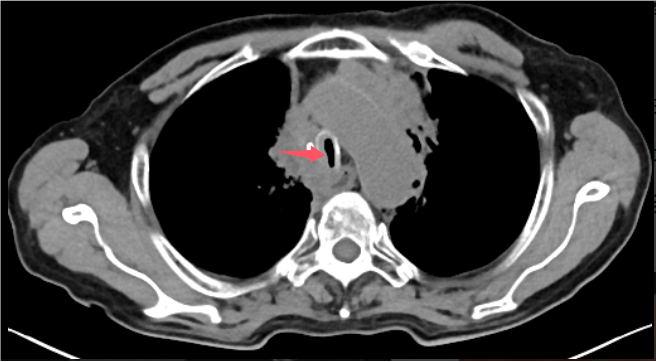

术前胸部CT见患者气道狭窄,呈一缝隙